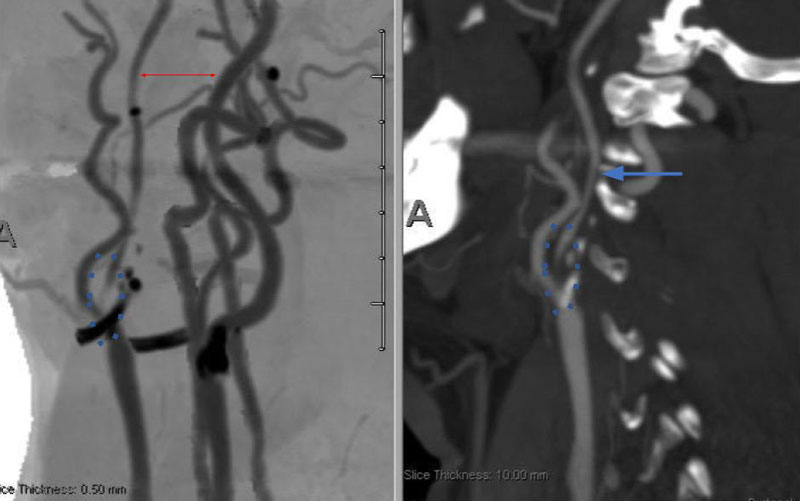

On admission, her initial CT scan was negative for stroke or hemorrhage, however a CTA demonstrated severe high grade 99% stenosis of the right Carotid bulb (ICA) with markedly diminished caliber of the cervical intracranial carotid artery secondary to calcified atherosclerosis without evidence of dissection (Figure 1).

Figure 1. A and B) CTA demonstrating severe ICA 99% stenosis (dotted) with flow-reduced diminution relative to the left ICA (red arrows) and distal plaque extension to C2 level.

Catheter cerebral angiography was then performed which demonstrated the 99% stenosis with distal vascular collapse and extension of the plaque superiorly into the mid third of the cervical right ICA (Figure 4). Interrogation for collaterals from the left ICA and posterior circulations demonstrated very small and minimal contributions from the anterior communicating artery and posterior communicating artery of the Circle of Willis.

Figure 4. A) DS Angiogram demonstrates severity and extent of plaque to C2-3 level (blue). B) And marked delay of ICA perfusion (yellow) relative to ECA branches (green).